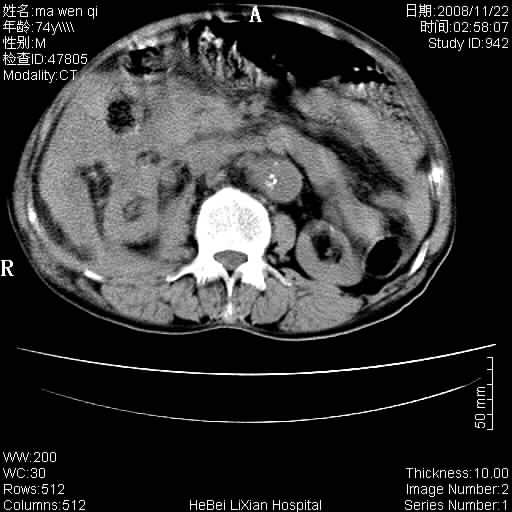

患者男 74岁.突然昏迷,休克6小时.血压70/30,头颅ct未见异常,既往体健.

补充病史,保留导尿10小时,尿袋内只有少许尿液,患者于住院后15小时后去世.

腹主动脉、双侧髂动脉夹层动脉瘤破裂出血进入腹腔。

1)考虑双侧髂动脉瘤并右侧动脉瘤破裂出血,右侧腹膜后及腹腔积血。2)双侧腹股沟疝。

1)考虑,腹主动脉、双侧髂动脉夹层动脉瘤破裂伴右侧腹膜后及腹腔积血。2)双侧腹股沟疝。

1)考虑胸、腹主动脉、双侧髂动脉瘤并右侧动脉瘤破裂出血,右侧腹膜后及腹腔积血。2)双侧腹股沟疝。